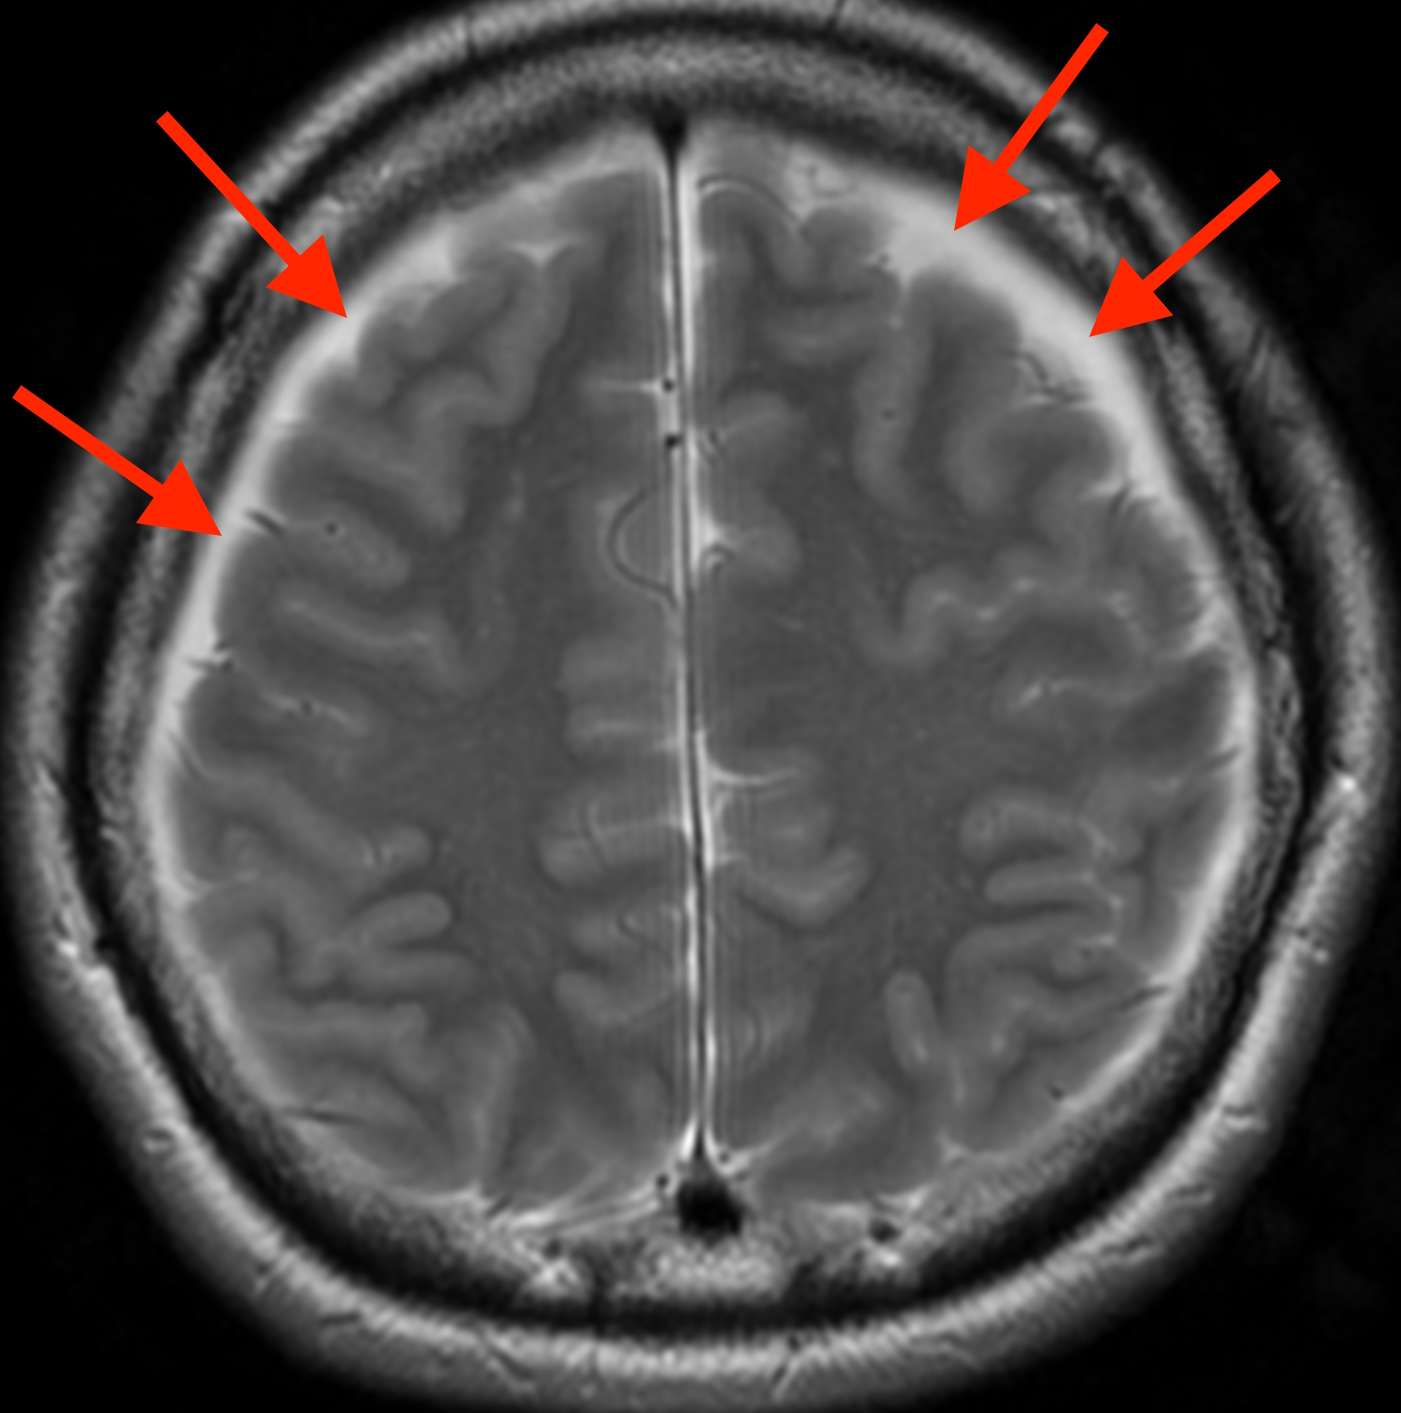

MRI検査をしたところ、

脳の周りにすき間(赤矢印)が見えています。このすき間の部分は血液が貯まったもので、「慢性硬膜下血腫」と言います。